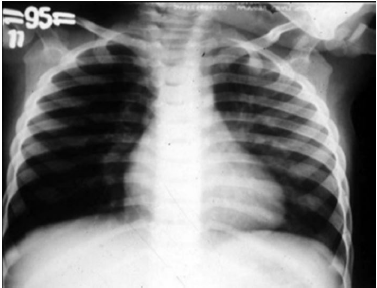

Um lactente de quatro meses de idade cronológica, nascido prematuro de vinte e nove semanas gestacionais, apresentou, durante o inverno, febre, tosse e dificuldade respiratória nos últimos três dias antes de ser levado por sua mãe à emergência pediátrica. A mãe relatou que a criança nunca havia apresentado um episódio semelhante a esse. O calendário vacinal mostrou que a criança recebeu duas doses da vacina antipneumocócica decavalente, porém não recebeu palivizumabe. O exame físico da criança mostrou desidratação, taquipnéia, retração intercostal e sibilos inspiratórios e expiratórios. O resultado do hemograma solicitado pelo médico revelou hematócrito de 40%, concentração de hemoglobina de 13 g/dL, 9.000 leucócitos/mm3, 55% de linfócitos, 34% de neutrófilos, 2% de eosinófilos, 1% de basófilos, 8% de monócitos, 340.000 plaquetas/mm3. O médico solicitou radiografia de tórax da criança, cuja imagem é apresentada na figura.